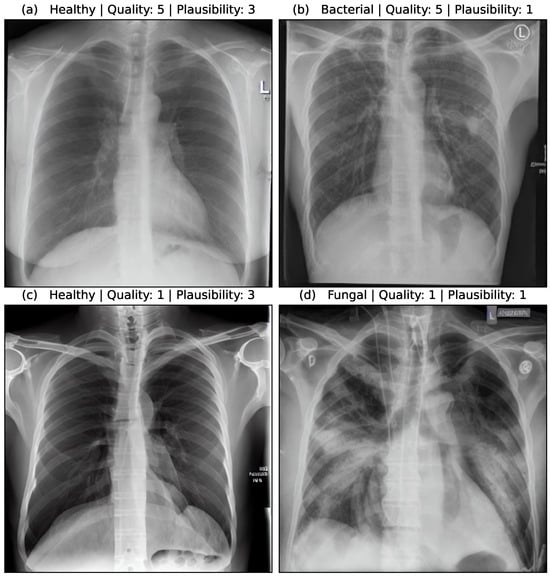

Figure 5 shows the assessment of four synthetic image samples with high/low quality and high/low plausibility scores. In (a, b) the anatomical structures are reproduced realistically and the proportions are accurate. The pleura, diaphragm, heart contour and hilar vessels are reproduced with absolute precision. The breast shadow is also reproduced exactly in (a), which simulates a woman as the gender of the patient. The quality rating is accordingly rated score 5 without any gradations. The healthy state in image (a) is shown regularly with a quality score of 5. The bacterial pneumonia in (b) is rather atypical, a suspect bronchial carcinoma from the simulated image is more realistic. It does not reflect peripheral inflammation in the sense of bronchopneumonia or lobar pneumonia, hence the assessment of plausibility as inappropriate (score 1). Image (c) appears artificial in appearance, the diaphragm contours, the heart silhouette and the bones are not realistically reproduced, the image quality is only rated with score 1. In contrast, no pathology of the lung parenchyma is recognizable, but this is still realistic and therefore rated as score 3 in terms of plausibility. Image (d) also appears artificial in appearance, in particular the hints of foreign material/lines and heart contours are unrealistic (quality score 1). The inflammations of the lungs described also seem unrealistic for any type of pneumonia; a fungal infection is unrealistically shown (plausibility score 1).

Figure 5. Medical assessment of quality and plausibility for 4 synthetic image samples. (a) Healthy case with high quality and plausibility. (b) Bacterial case with high quality but low plausibility. (c) Healthy case with low quality but high plausibility. (d) Fungal case with low quality and plausibility.